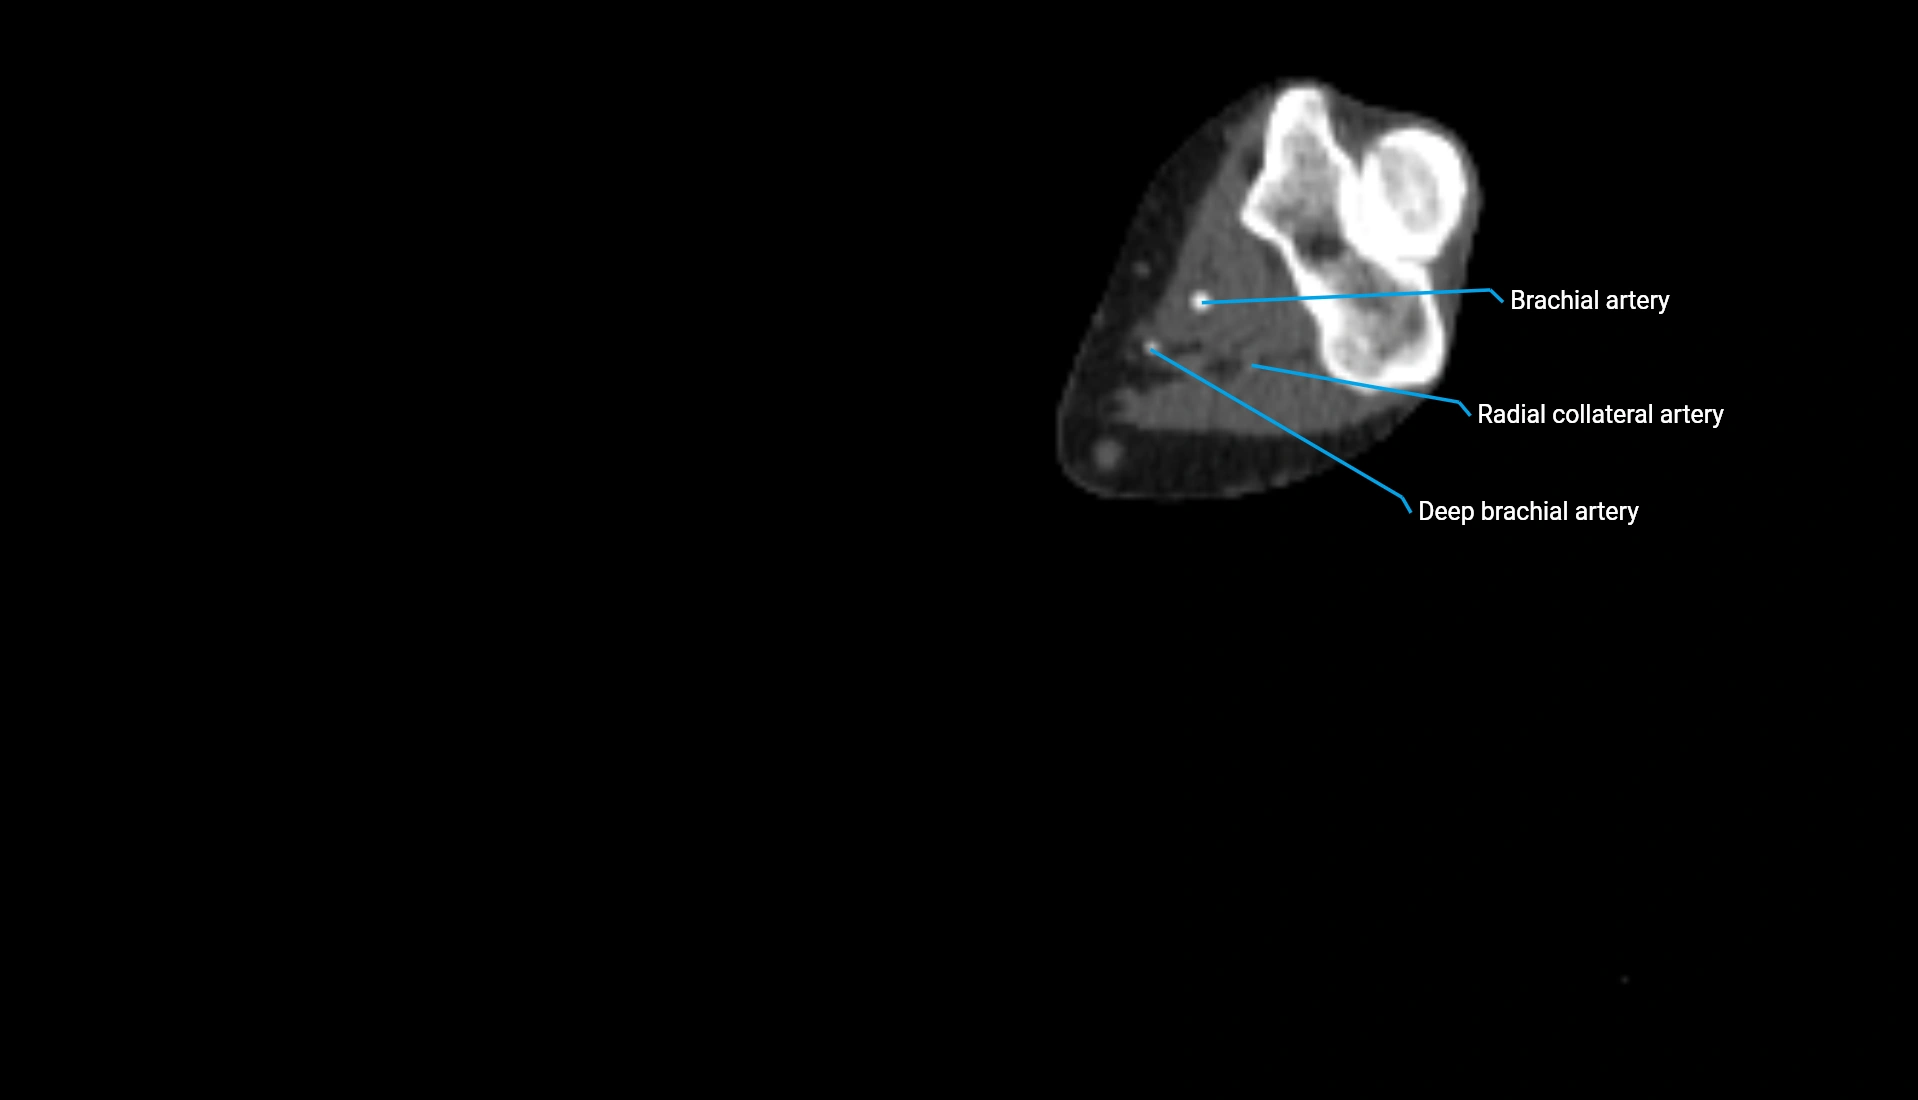

CT Appearance

Non-Contrast CT:

• Cortex: High-density, sharply defined

• Subchondral bone: Dense cancellous matrix

• Articular surface: Smooth concave contour articulating with the capitellum

• Excellent for evaluating bone integrity, alignment, and subtle fractures